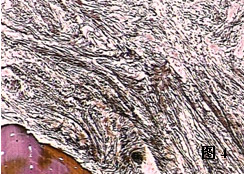

2) 中期骨髓萎縮與纖維化期纖維組織增生突出,占骨髓的40%~60%,造血細胞占30%,巨核細胞仍增生。骨小梁增多,增粗,與骨髓相鄰部位有新骨形成。各個散在造血區域被由網狀纖維、膠原纖維、漿細胞和基質細胞形成的平行束狀或螺鏇狀物質分隔。

3) 晚期骨髓纖維化和骨質硬化期 MF終末期。以骨質的骨小梁增生為主,占骨髓的30%~40%。纖維及骨質硬化組織均顯著增生,髓腔狹窄,除巨核細胞仍可見外,其他系造血細胞顯著減少。此期骨髓基質成分中聚合蛋白為主,主要表現纖維連線蛋白,外連線蛋白和TENASCIN分布增加。

(二)骨髓塗片及活檢 骨髓穿刺約有1/3的病例呈現\乾抽\現象。骨髓塗片有核細胞增生低下,也可表現為增生性骨髓象。骨髓活檢找到大量網狀纖維組織,為診斷本病依據。根據骨髓中保留的造血組織和纖維組織增生的程度不同,骨髓病理改變可分為三期:①早期全血細胞增生伴輕度纖維組織增生;②中期骨髓萎縮和纖維化;③晚期骨髓纖維化和骨質硬化。

2、中期骨髓萎縮與纖維化期:纖維組織增生突出,占骨髓的40%-60%,造血細胞占30%,巨核細胞仍增生。骨小梁增多、增粗,與骨髓相鄰部位有新骨形成。各個散在造血區域被網狀纖維、膠原纖維、漿細胞和基質細胞形成的平行束狀或螺鏇狀物質分隔。

發性骨髓纖維化的依據;有關專家會根據骨髓中保留的造血組織和纖維組織增生的程度不同,將骨髓病理改變可分為三期:早期全血細胞增生伴輕度纖維組織增生;

中期骨髓萎縮和纖維化;晚期骨髓纖維化和骨質硬化。